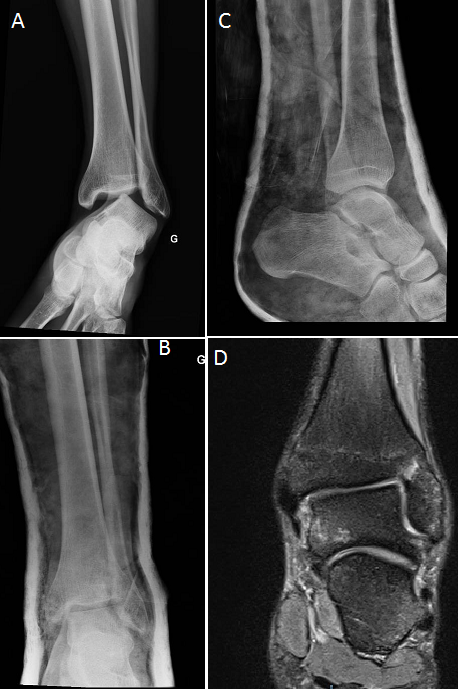

Nous rapportons le cas d'un sportif de 20 ans victime d'un accident de hand-ball occasionnant une luxation pure de la cheville (A). La réduction a été pratiquée en urgence sous anesthésie générale, la radiographie et le scanner de contrôle après réduction avaient objectivés une bonne congruence articulaire (B, C). Une contention par une botte plâtrée fut assurée pendant six semaines. L'examen de la cheville réalisé après l'ablation du plâtre n'a pas retrouvé une laxité de la cheville et l'IRM de la cheville réalisée à la recherche d'une lésion ligamentaire avait objectivée une intégrité des ligaments péri-articulaire (D). Après un recul de neuf mois, les résultats fonctionnels étaient excellents, sans signes d'instabilité ni d'arthrose.La luxation tibio-talienne sans fracture malléolaire associée est une lésion très rare, souvent causée par un traumatisme de haute vélocité, jusqu'à l'heure actuelle, peu de cas ont été rapportés dans la littérature.La rareté de cette lésion peut être expliquée par la durabilité des ligaments par rapport aux malléoles et donc lors d'un traumatisme de la cheville une fracture se produise plutôt qu'une luxation.